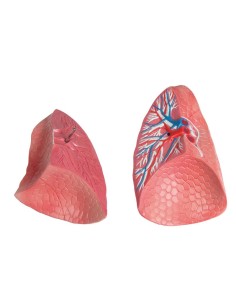

Des modèles anatomiques détaillés pour tous les besoins

Du crâne en 22 parties à verrouillage magnétique aux modèles de colonne vertébrale, des modèles d'articulation aux modèles de cœur, chaque pièce de notre collection est conçue pour une immersion totale dans l'étude de l'anatomie humaine. Nos modèles, réalisés à partir de scans d'os réels, garantissent une expérience tactile authentique et une fidélité de poids presque identique aux originaux.